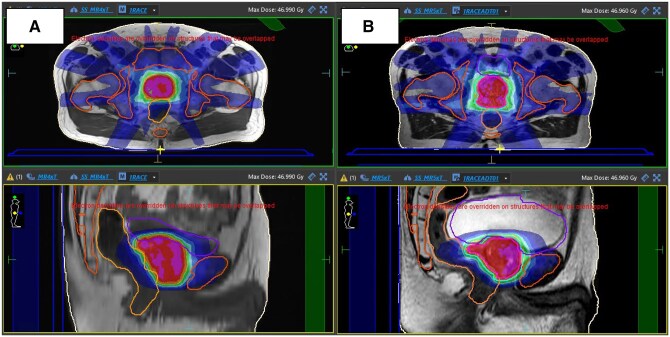

Methods: We audited prostate cancer patients treated with 5-fraction (#) stereotactic body radiotherapy (SBRT) between March 2023 and January 2024, assessing dMRI for RT planning suitability. Planning suitability required a T2-weighted sequence for target/organs at risk (OAR) delineation and a large field-of-view (LFOV). Scans were classified as RT plan suitable or as having specific issues (incomplete body coverage or slice thickness >10 mm). Workflow analysis from RT referral to first fraction estimated potential time savings with simulation-free RT (SFRT). Case studies illustrated identified issues and proposed solutions.

Results: dMRIs were available for 93% of patients, with scans originating from various hospitals and conducted on 1.5 Tesla (T) or 3 T MRI scanners. Ideal image characteristics for RT planning were met in 38% of MRIs. Issues such as cropped field of view (FOV) and low slice resolution were identified, but proposed solutions could increase the number of patients with suitable scans to 87%.